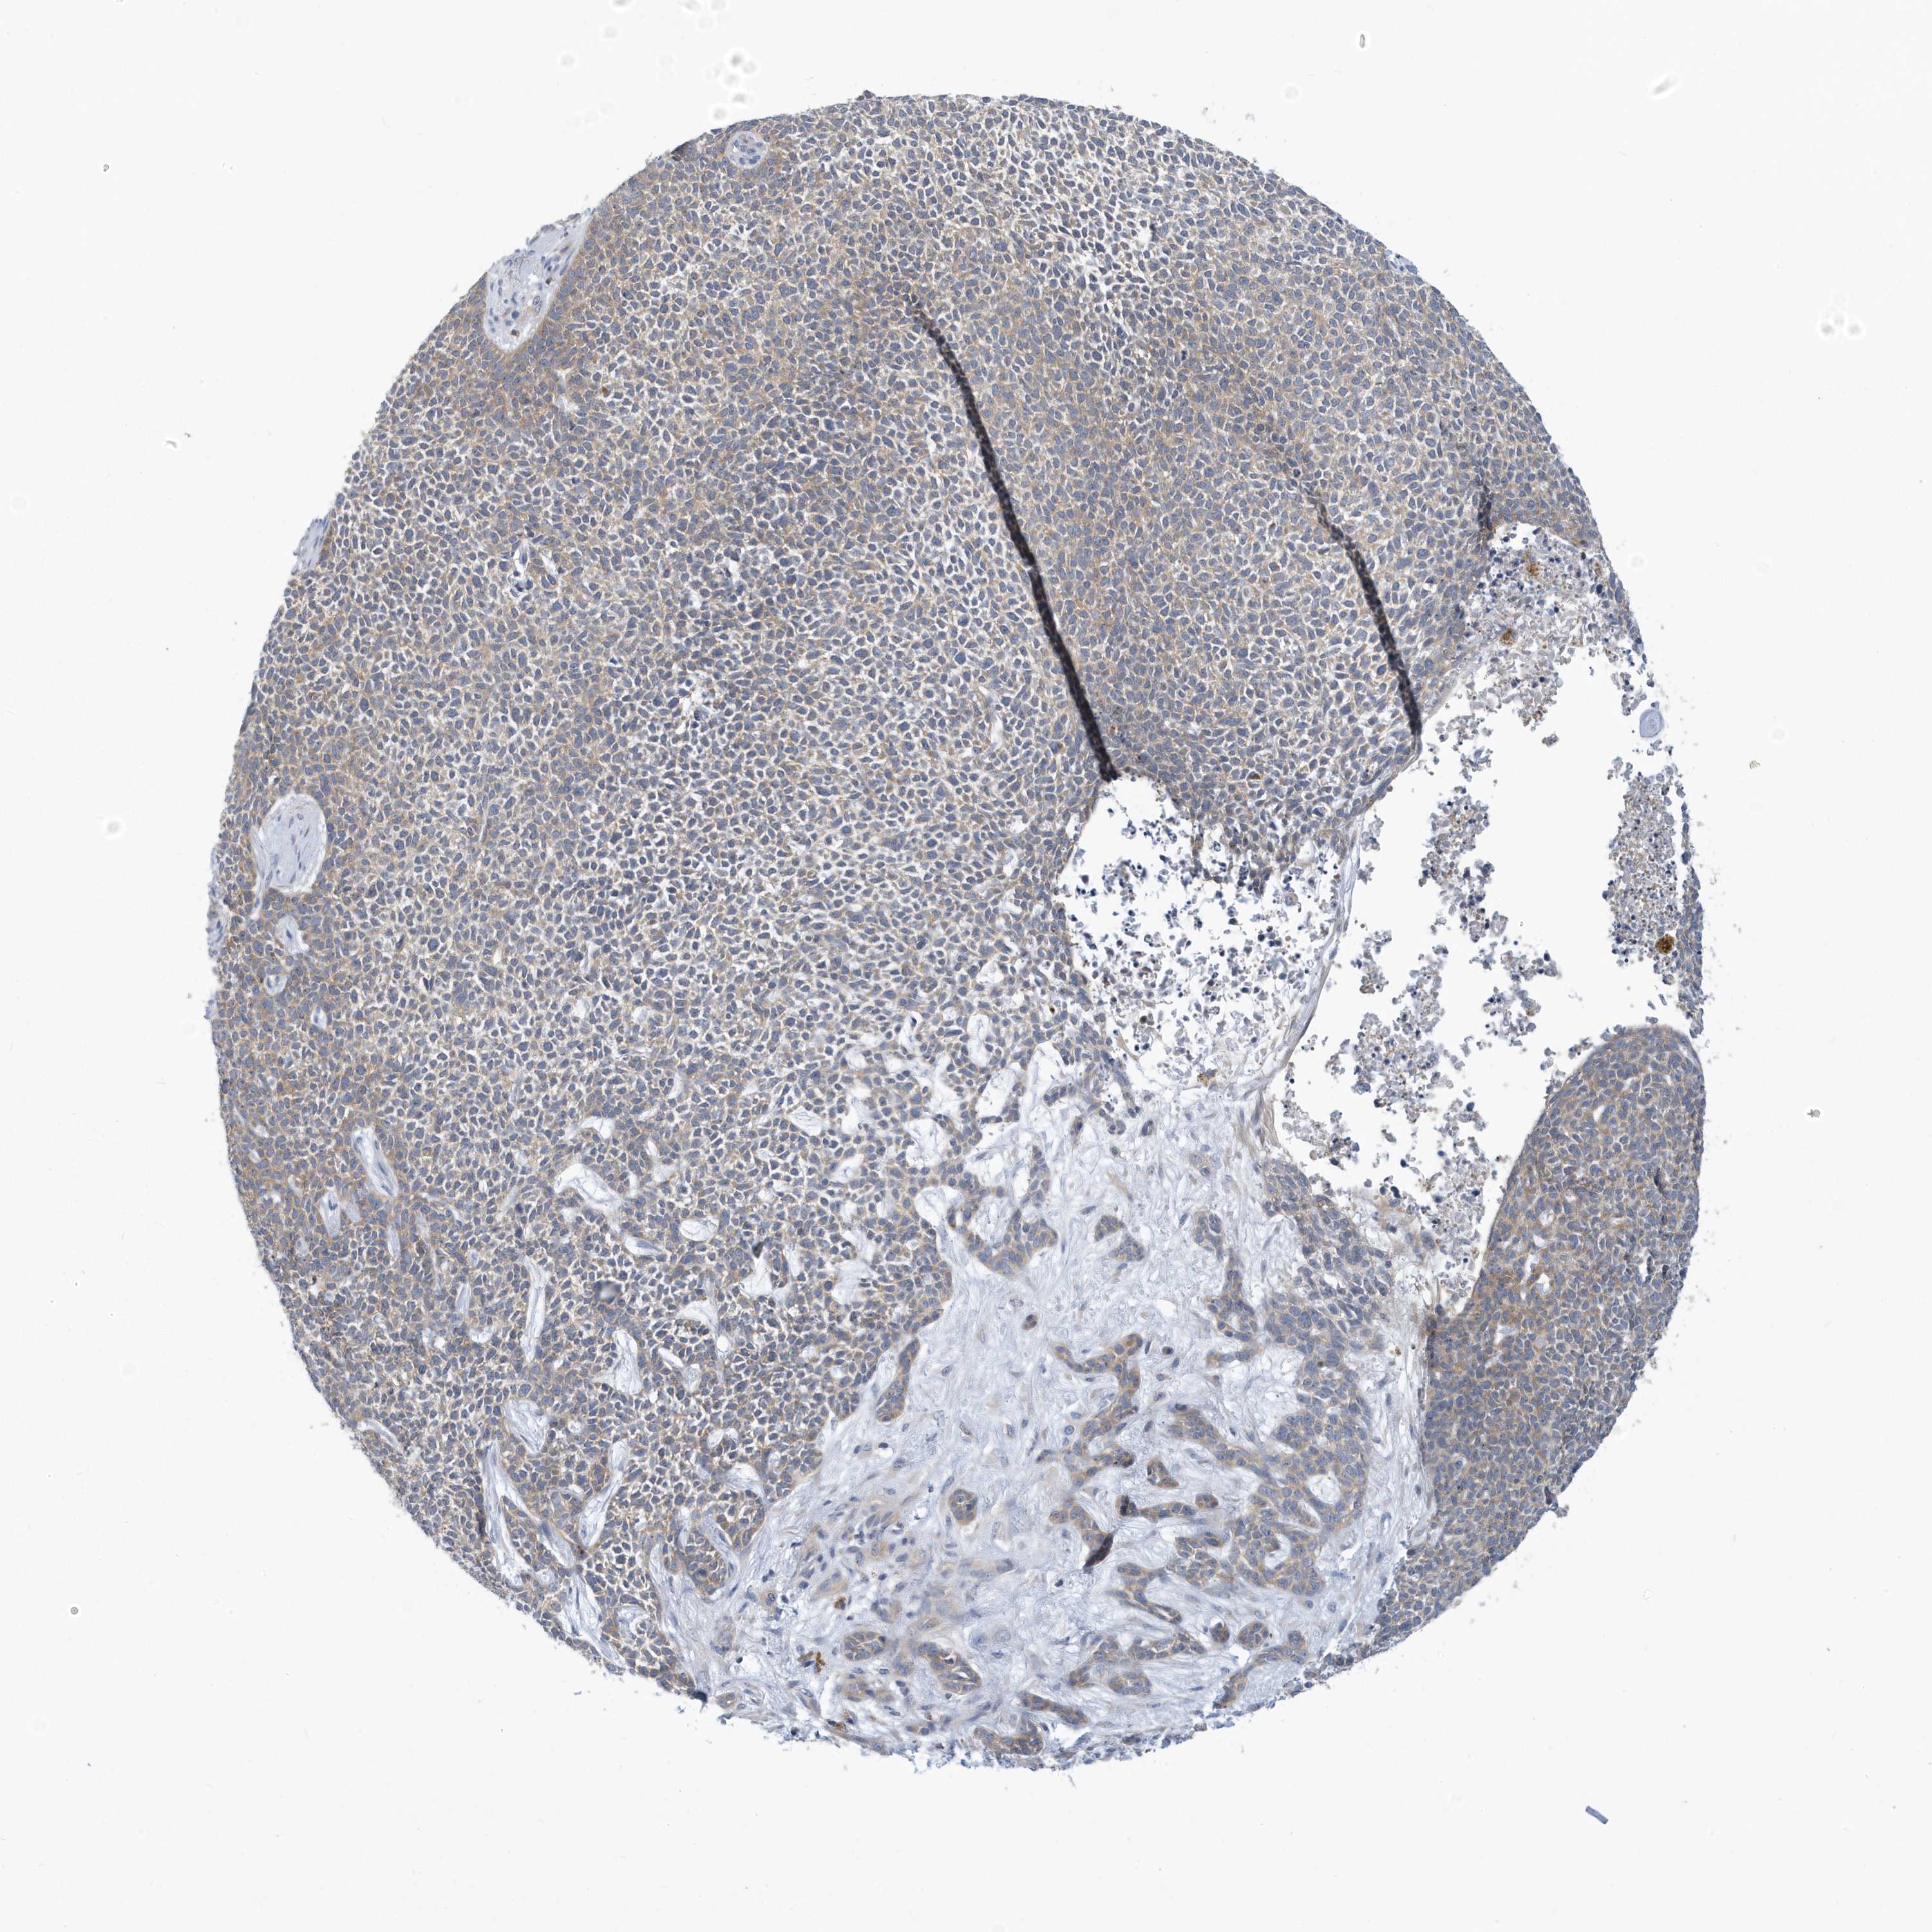

Basal cell and squamous cell cancer

SKIN CANCER - Protein expressioni

A mouse-over function shows sample information and annotation data. Click on an image to view it in a full screen mode. Samples can be filtered based on level of antibody staining by selecting one or several of the following categories: high, medium, low and not detected. The assay and annotation is described here.

Each image is clickable and will lead to virtual microscopy that enables deeper exploration of all samples and also displays staining intensity scores, fraction scores and subcellular localization as well as patient and tissue information for each sample.

Antibody HPA030968

Staining

High

Medium

Low

Not detected

Intensity

Strong

Moderate

Weak

Negative

Quantity

>75%

75%-25%

<25%

None

Location

Nuclear

Cytoplasmic/membranous

Cytoplasmic/membranous,nuclear

Squamous cell carcinoma, metastatic, NOS